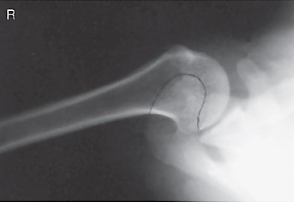

name the projection and rotational; label the part of the humerus the arrow is pointing to

AP internal, lesser tubercle